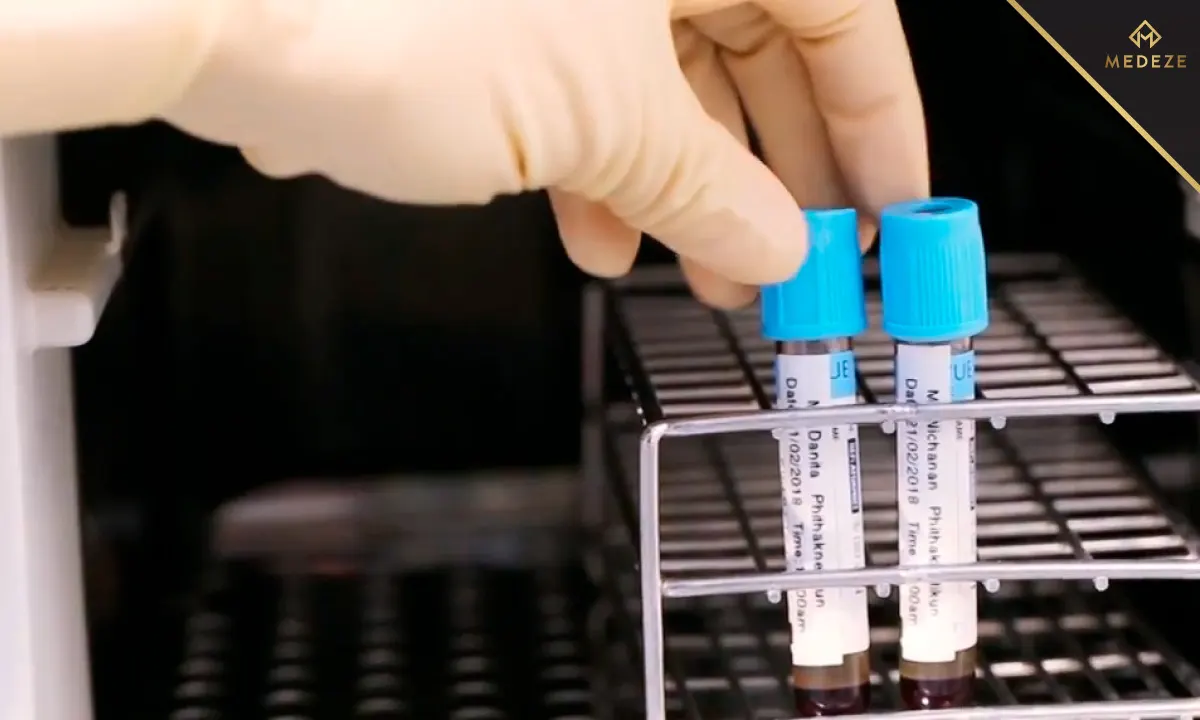

ในปัจจุบันมีเทคโนโลยีที่ก้าวไกล ที่สามารถให้บริการตรวจเลือดเพื่อตรวจสอบระดับการทำงานของ NK Cell ซึ่งเป็นกุญแจสำคัญที่บ่งชี้ถึงสภาวะภูมิคุ้มกันโรค วิธีการนี้เราทดสอบโดยใช้เลือดเพียง 1 ml ตัวอย่างของเลือดจะถูกส่งไปยังห้องปฏิบัติการ เพื่อดูว่า NK Cell ทำงานได้ดีเพียงใดเมื่อเจอกับสิ่งแปลกปลอม การทดสอบนี้ใช้เวลาเพียงแค่ 72ชั่วโมง ผลลัพธ์ที่ได้จะช่วยแพทย์ประเมินความเสี่ยงของคุณต่อการเกิดโรคและมะเร็ง